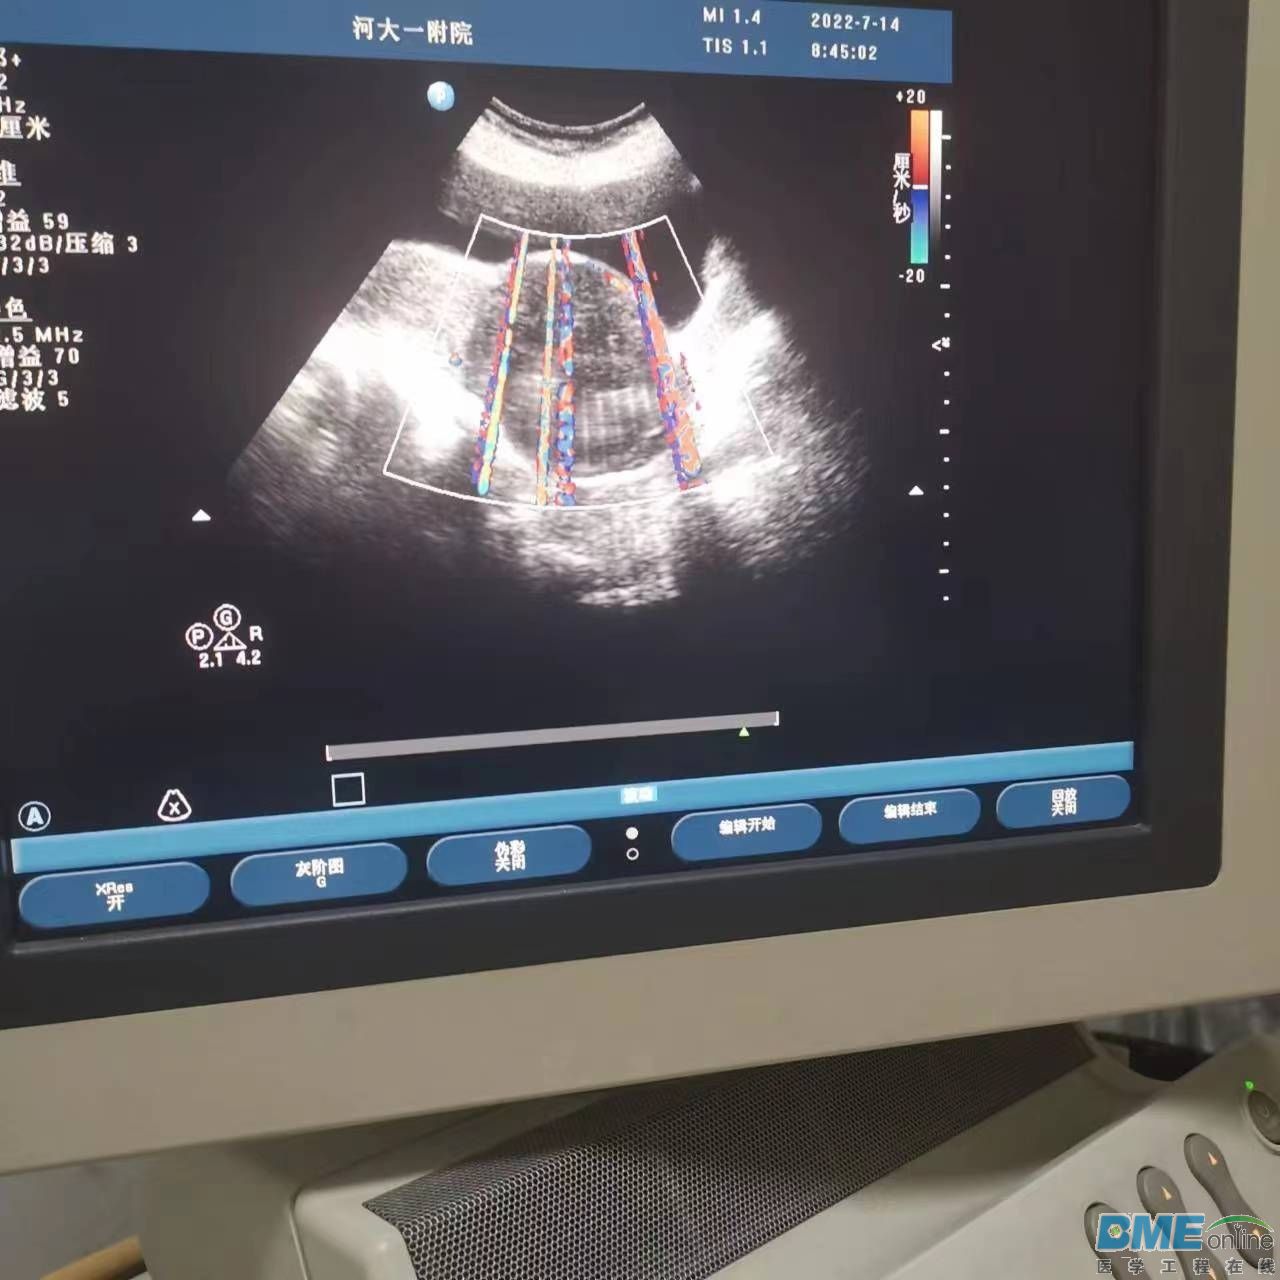

飞利浦超声这种图像是什么问题?

请教各位老师,请问这种图像是什么电路板问题?